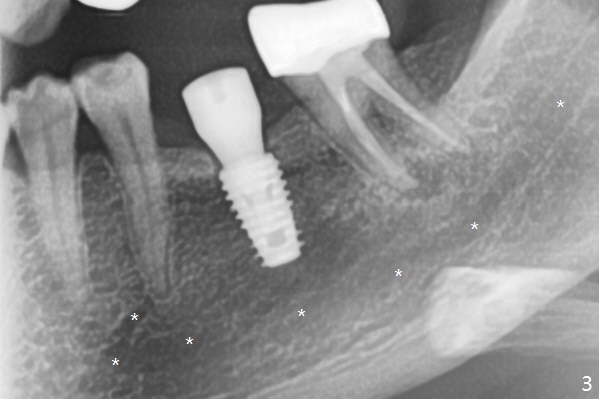

With one carpule of Xylocaine (34 mg with 17 mcg of Epinephrine), a 5x8.5 mm implant is placed at #19 in a timely and painless manner. The patient is pleased as compared to her previous implant placement at #3 and 30. Due to the thin buccal bone, the implant is placed ~.5 mm deeper than designed; a 6.5x4(2) mm healing abutment is incompletely seated (Fig.1). A smaller and skinny one (5.5x7(4) mm) is seated normally (Fig.2). Regional panoramic X-ray shows clearance from the Inferior Alveolar Canal (Fig.3 *). Although there is crestal bone resorption 6 months postop, the bone density next to the 1st thread is high (Fig.4 >). A 5.5x4(4) mm cemented abutment is placed for impression. The patient returns with #18 crown dislodgement and #19 crown loosening 11 months post cementation (Fig.5 <: gap between implant and abutment). Since the crown and abutment are unable to be torqued properly, they are removed (Fig.6). A narrower abutment is able to be seated apparently completely while a metal post (Fig.7 *) is tried in in the distal root of #18. To reduce the chance of re-fracture of #18 crown, the tooth #15 needs to be distalized orthodontically so that an implant will be placed at #14 (Fig.5).